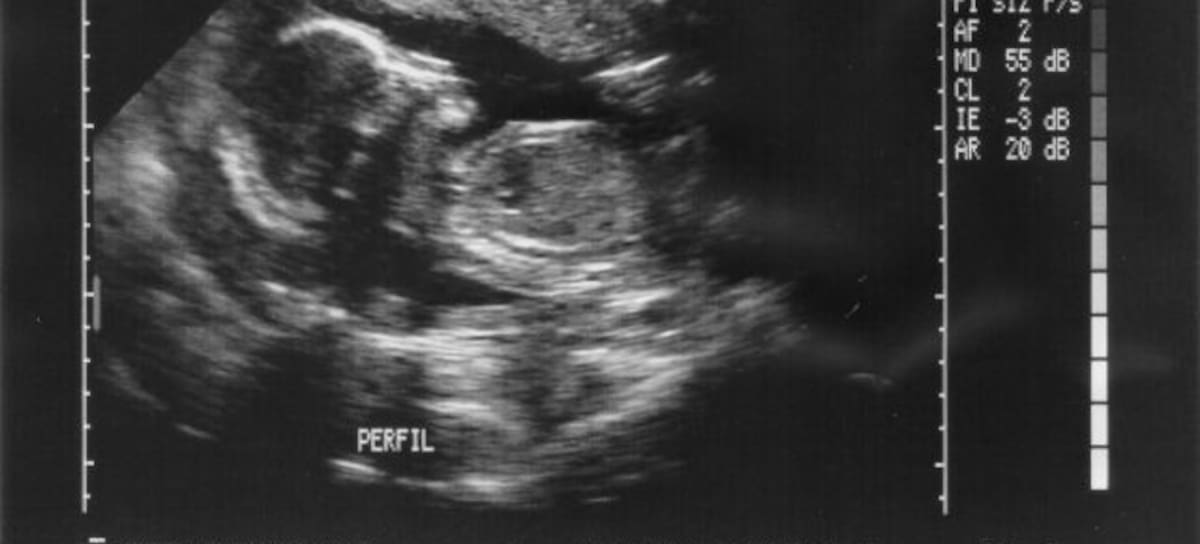

Una pareja en Washington se sometió a una prueba de paternidad cuando se dieron cuenta que la sangre de su hijo no coincidía con ninguno de ellos.

Después fueron a hacerse otra prueba en la que resultó que el “padre” del niño en realidad era su tío, ya que sólo 10% de sus genes se parecían, lo que los médicos concluyeron fue que el verdadero padre del niño genéticamente era el hermano gemelo del “papá”, pero este no nació.

Este extraño caso es el primer caso registrado de “quimera humano”: genes adicionales de un mellizo, cuyo ADN fue absorbido por el cigoto superviviente mientras aún se encontraba en el vientre materno.